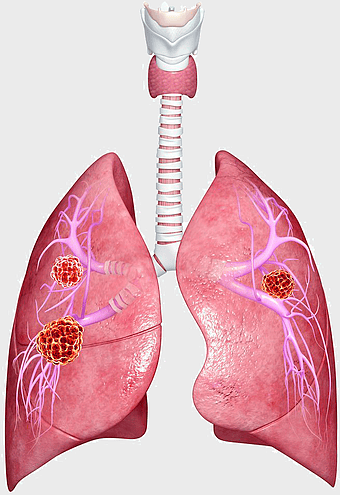

Pulmonary edema symptoms, chronic obstructive pulmonary disease diagram, kidney failure effects on lungs, pulmonary circulation illustration, lung disease diagnostic, respiratory health visuals, human anatomy respiratory system, PNG

- pulmonary edema symptoms

- chronic obstructive pulmonary disease diagram

- kidney failure effects on lungs

- pulmonary circulation illustration

- lung disease diagnostic

- respiratory health visuals

- human anatomy respiratory system

lung cancer metastasis, human lung anatomy, pulmonary carcinoma cells, prognosis of lung cancer, respiratory disease illustration, medical oncology, thoracic organ health -

lung cancer screening, human lung anatomy, nonsmall cell lung cancer, thorax medical imaging, respiratory system health, pulmonary diagnostics, oncology visualization -